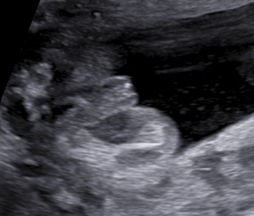

Vyšetření časného těhotenství NT screening Downova syndromu v 1.trimestru Screening vrozených vad ve 2. trimestru Screening ve 3. trimestru

Používáme špičkové přístroje a všichni naši lékaři jsou držiteli certifikátu Fetal Medicine Foundation (FMF) na všechny typy ultrazvukových vyšetření v těhotenství. Při vyšetření miminka se vždy řídíme FMF protokoly, prohlížíme i drobné detaily a ke zpřesnění používáme kombinaci 2D a 3D ultrazvuku. V průběhu vyšetření vám vždy vysvětlujeme, co právě vyšetřujeme a co s námi můžete vidět na monitoru. Po skončení vyšetření vám srozumitelně vysvětlíme výsledky (a případně závažnost situace) a navrhneme další postup.